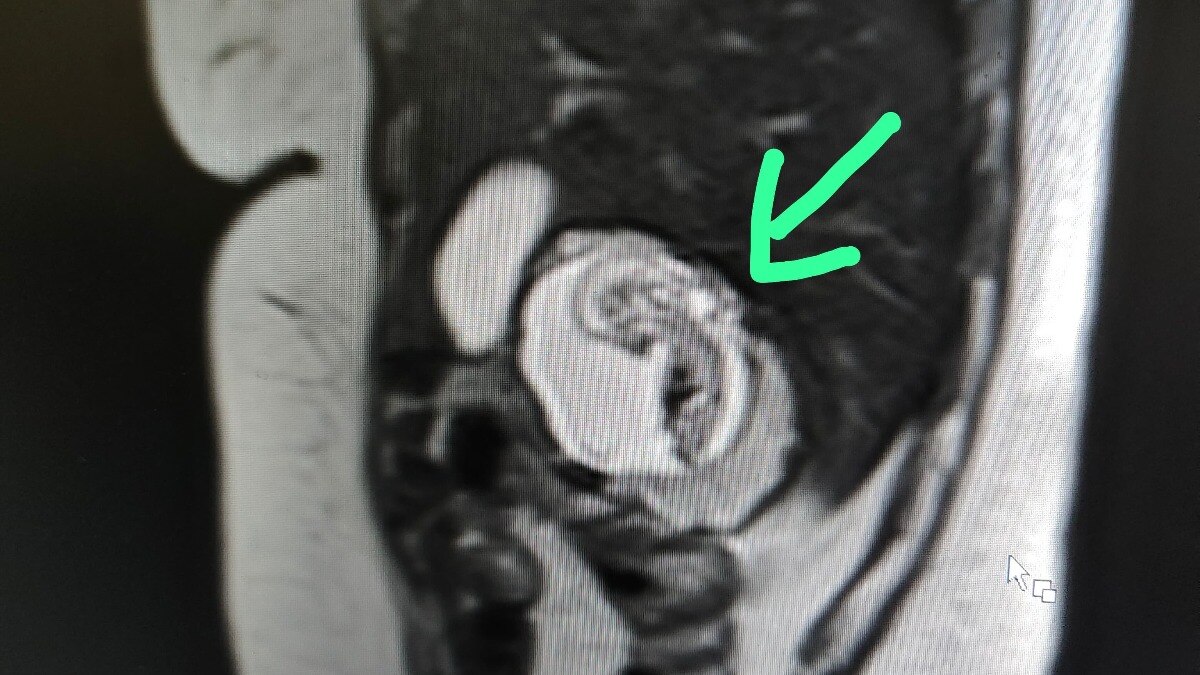

जब महिला का दर्द असहनीय हो गया, तो उसे एक निजी इमेजिंग सेंटर पर पूरे पेट के एमआरआई (MRI) जांच के लिए भेजा गया. रेडियोलॉजिस्ट डॉ. केके गुप्ता ने जब एमआरआई की रिपोर्ट देखी तो उनके होश उड़ गए. जांच में साफ पता चला कि 12 हफ्ते का गर्भ, जिसकी धड़कन भी स्पष्ट थी वह गर्भाशय में न होकर सीधे महिला के लीवर के दाहिने भाग में पल रहा था.

डॉ. केके गुप्ता ने इस घटना की पुष्टि करते हुए बताया कि 22 जुलाई को यह महिला एमआरआई के लिए आई थी. उन्होंने कहा, "महिला दो महीने से पेट दर्द और उल्टी से परेशान थी. जब हमने उसका एमआरआई की तो पाया कि उसके लीवर में 12 हफ्ते की प्रेगनेंसी है, गर्भ की धड़कन भी थी और वह 12 हफ्ते का पूरा विकसित गर्भ था."